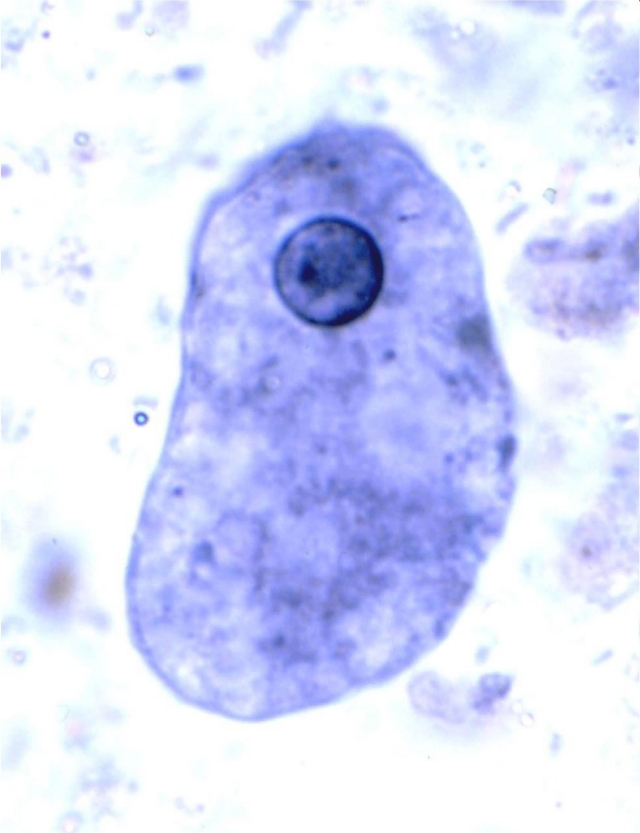

Trophozoite of Entamoeba histolytica

Trophozoite of Entamoeba histolytica, containing RBCs